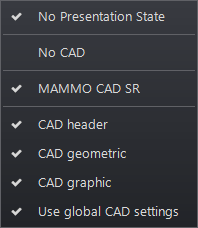

CAD Overlays

If a study includes a CAD marker, the presentation state icon (highlighted) appears in the top left corner of the image when it is displayed in an image frame.

Selecting the presentation state icon reveals a dropdown menu consisting of current presentation state functions (show or hide):

When applied, these functions override the current CAD marker display state applied to each individual image using the image frame’s presentation state tool. When mammography CAD graphic and geometric overlays exist for an image, apply any of the options to just one image by selecting the applicable option from the list.

| Function | Description |

| CAD header | Heading on image indicating supported manufacturers and systems |

| CAD graphic | CAD marker header and only graphic overlays appear on each image. Available when both graphic and geometric overlays exist |

| CAD geometric | CAD marker header and only geometric overlays appear on each image. Available when both graphic and geometric overlays exist |

The default CAD overlay settings can be configured from the Tools/Mammo menu under Mammography CAD.